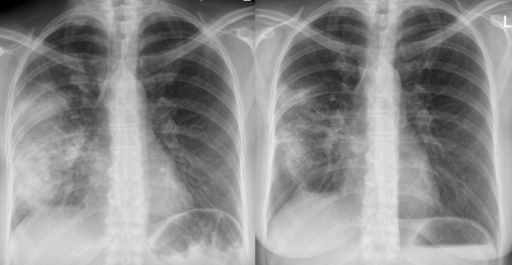

Radiographie pulmonaire

A definitive diagnosis of CAP requires evidence of consolidation on a chest x-ray (CXR). Therefore, it is recommended to perform a CXR for all patients admitted to hospital as soon as possible, ideally within 4 hours of admission.

Radiographic image of pneumonia before (left) and after (right) antibiotic therapy

Acute pneumonia

Hellerhoff, CC BY-SA 3.0, via Wikimedia Commons